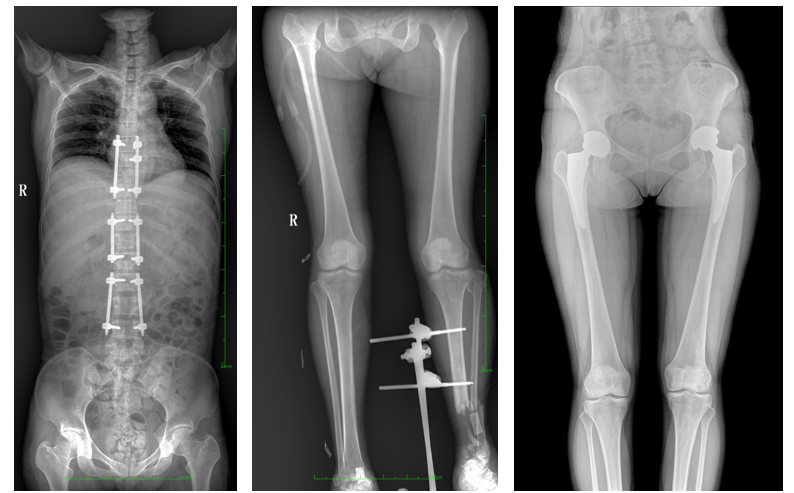

普愛醫(yī)療自主研發(fā)的一款數(shù)字化X光機(jī)——PLX8600大視野平板動(dòng)態(tài)DR,擁有43cm*86cm超大有效視野,可一次性拍攝全脊柱、雙下肢的影像視野。使全脊柱及雙下肢能夠得到完整清晰的成像,為臨床在脊柱側(cè)彎畸形和下肢骨關(guān)節(jié)病變?cè)\斷、治療方案制定及治療后復(fù)查提供精準(zhǔn)的測量。